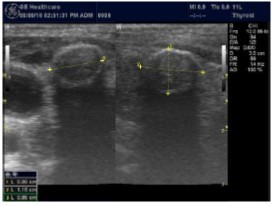

The reported prevalence of nodular thyroid disease depends on the population studied and the methods used to detect nodules 16. Our study population is unique as it is composed entirely of ESKD patients. We also used ultrasound as a method of detecting thyroid abnormalities. In our study the prevalence of thyroid nodular pathology as detected by ultrasound was found to be 57.6% mirror image what reported in the literature as it has been reported that nodules found on ultrasonography suggest a prevalence of 19 to 67%17, 18; and in other publications it has been reported to range from 50% to 70% 7, 8. Figure 3A below shows an Ultrasound detected thyroid nodule.

The prevalence of thyroid nodule is also influenced by age. In one study, 30 % of subjects 19 to 50 years of age had an incidental nodule on ultrasonography19. However, from our work we found that the presence of nodules increases with age. This may explain the reported low incidence of thyroid nodule in the age group 19-50 years. Also, with the widespread use of sensitive imaging in clinical practice, incidental thyroid nodules are being discovered with increasing frequency.

High-resolution ultrasonography (USG) is the most accurate and cost-effective method for evaluating and observing thyroid nodules 3. Although there is some overlap between ultrasound appearance of benign and malignant nodules, certain USG features are helpful in differentiating the two. Iso-or hyper-echogenicity of the thyroid nodule in conjunction with a spongiform appearance is the most reliable criterion for benignity of the nodule on gray-scale ultrasound, Figure 4A. Other features like nodule size <1 cm, width > length, presence of hypoechoic or hyperoechoic halo around the nodule, Figure 4A and Figure 4B, caused by fibrous capsule compressing thyroid tissue, and coarse/curvilinear calcification are less specific but may be useful ancillary signs4 ,6. "Ring down" or "comet-tail" artifact or sign is typical of benign cystic colloid nodule, Figure 520. Perinodular flow or spoke-and-wheel-like appearance of vessels on color Doppler examination is characteristic of a benign thyroid nodule. However, this flow pattern may also be seen in thyroid malignancy. A complete avascular nodule is very unlikely to be malignant 4.

Figure 4B.Isoechoic nodule with Hyperechoic rim